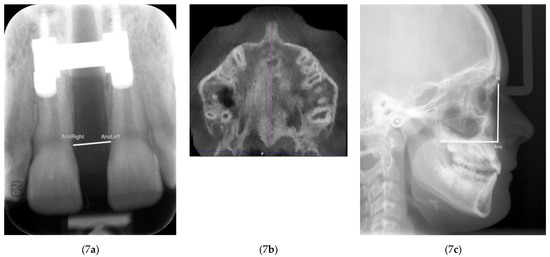

2. Materials and Methods

3. Results